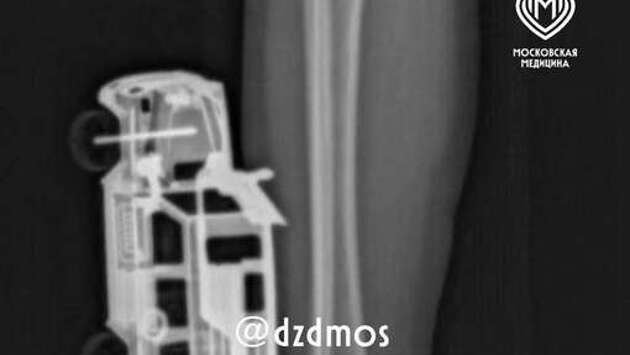

В Москве врачи спасли мальчика с игрушечной машинкой в ноге

В Москве четырехлетний мальчик упал на игрушечную машинку и оказался в больнице. Об этом сообщает Telegram-канал "Московская медицина". По словам родителей, ребенок прыгнул с кровати у себя дома и неудачно упал на игрушку правой голенью. Машинка повредила мягкие ткани, ее части вошли глубоко и достигли подкожножировой клетчатки. Пострадавшего мальчика доставили в больницу, где ему сделали рентген, чтобы исключить повреждение костей. После этого медики удалили игрушку и провели хирургическую обработку образовавшейся на ноге ребенка раны. Через сутки малолетнего пациента уже выписали домой. До этого на Урале врачи спасли ребенка с куском глины в бронхах. Мальчик отковырял кусочек от деревенской печки и закашлялся, поперхнувшись.